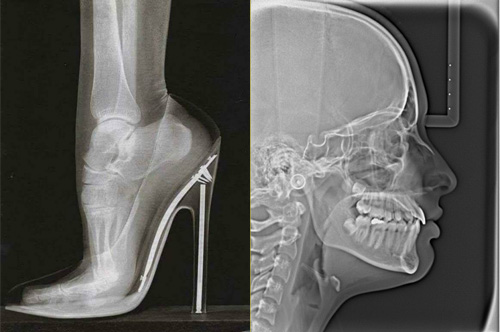

DentalArt oferuje również zdjęcia cefalometryczne (boczne) – przydatne i często wymagane przy leczeniu ortodontycznym.

- zdjęcie cefalometryczne 70zł